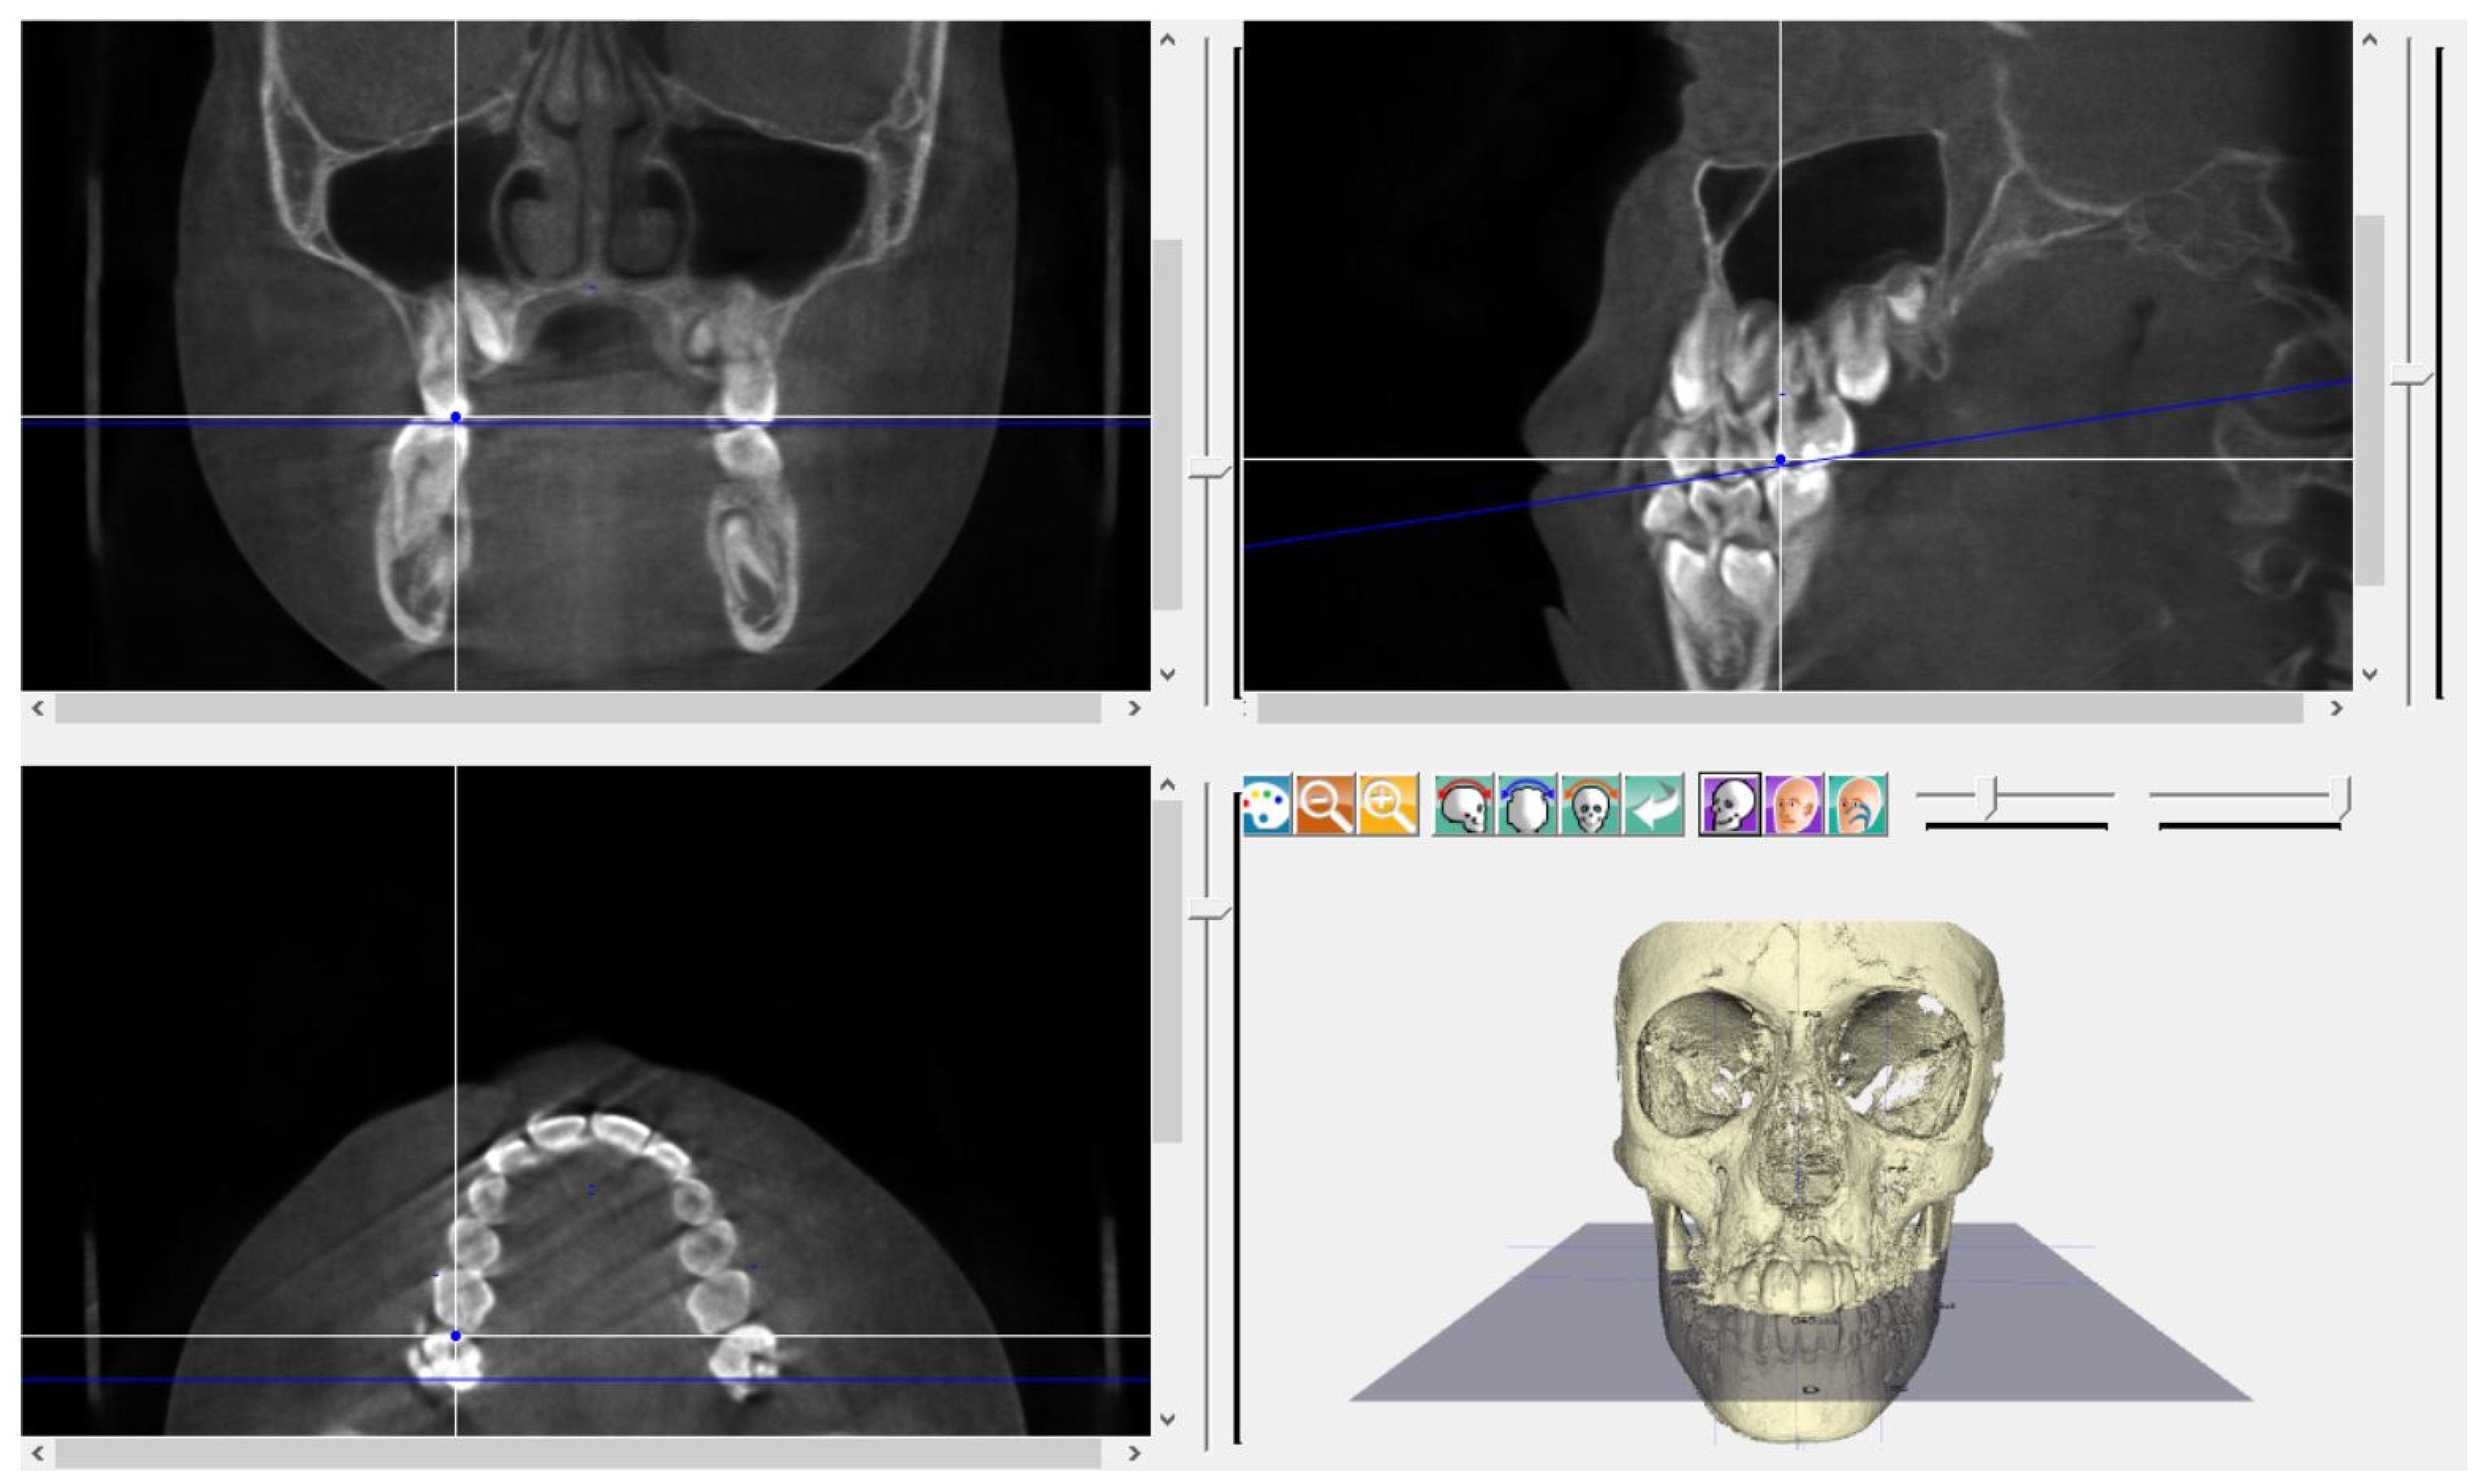

Bone Modifications Induced by Rapid Maxillary Expander: A Three-Dimensional Cephalometric Pilot Study Comparing Two Different Cephalometric Software Programs

2. Materials and Methods